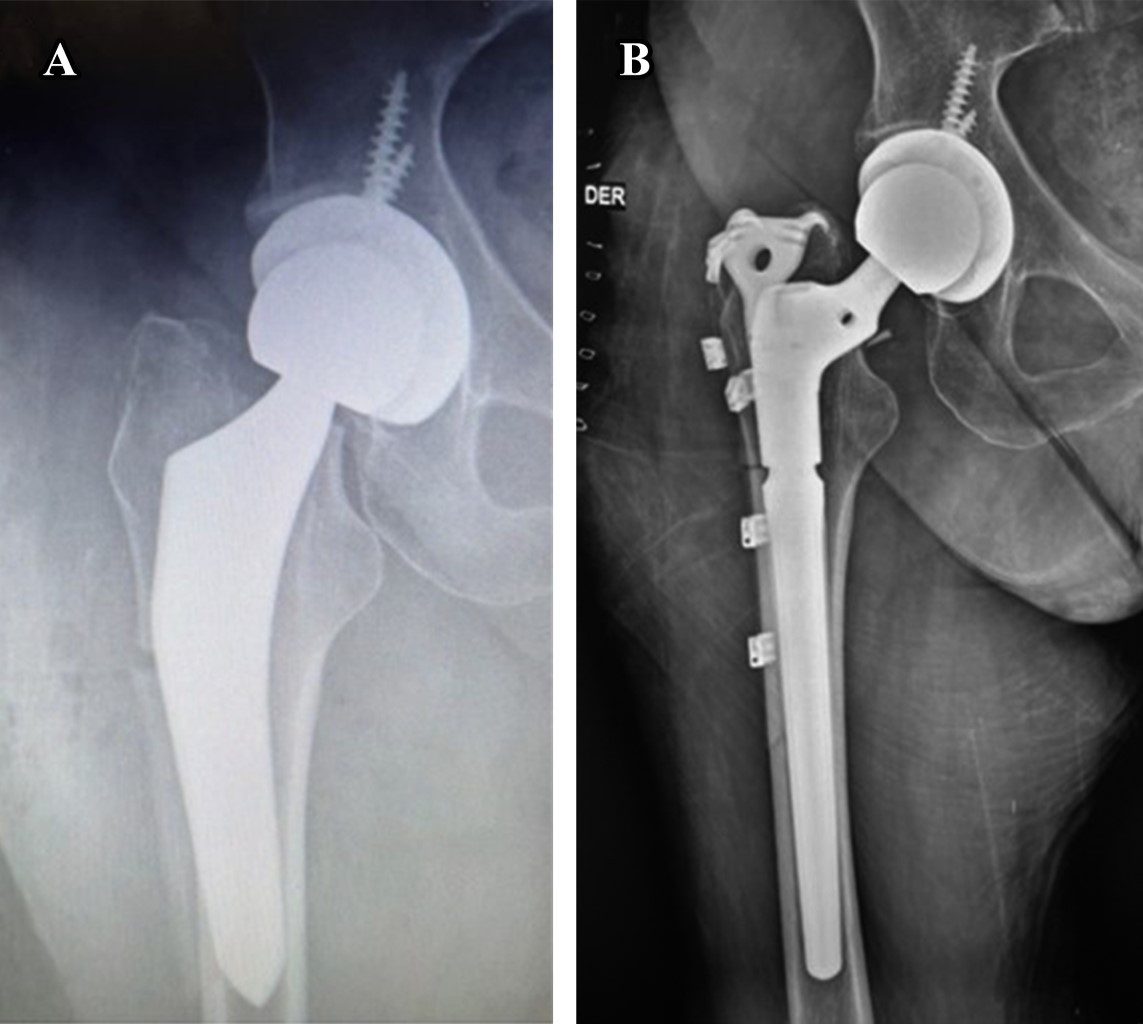

In some cases, an infection could be related as part of the wound complications, and in very few cases, surgical management is required. Periprosthetic infection is a catastrophic complication. It should be resolved according to standard protocols depending on the presentation and diagnosis, often requiring surgical management with implant retention or exchange in one or two stages. Wound problems are one of the most common complications related to the anterior approach, and superficial wound breakdown can occur early in the postoperative period (Figure 7). Meticulous care should be taken with hemostasis at the end of the procedure because the only formally closed layer is the superficial fascia of the TFL. We use continuous absorbable sutures to ensure a good seal after any bleeders are coagulated.

A wound hematoma formation in the DAA could be the result of a direct bleeding source, such as an inadequate ligation of the external circumflex vessels or the posterior circumflex vessels that could be damaged during the femoral neck osteotomy of the tensor fascia lata muscle injury, this bleeding may be greater than in other approaches. Direct skin damage during femoral reaming is expected at the beginning of the learning curve. In obese patients, the incision must be large enough to prevent contact with the reamer with the soft tissues.

Postoperative fractures can result from direct trauma and should be treated according to the classification and management of periprosthetic fracture protocols. Some non-identified fractures could be produced during the procedure and present in the former days as complex, unstable fractures with stem compromise, minor or severe subsidence that could need former revision and stem removal and exchange (Figure 8).